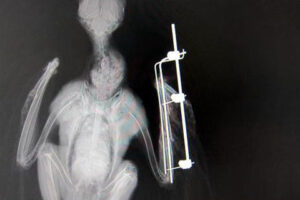

レントゲン検査を行った結果、左前腕の橈骨(とうこつ)と尺骨(しゃっこつ)を複合骨折(数カ所で骨折)していました。尺骨(鳥類では通常太い方の骨)は二カ所で斜めに折れ、ギプスなどによって外側から固定するだけでは整復するのが難しいと判断されました。

複雑にピンを入れて固定

ガス麻酔によって眠らせた後、手術によって橈骨と尺骨の内部にピンを入れ、さらに捻転しないように外側からもスクリューピンを打ち込んで折れた骨をつなげました。バラバラ折れていた尺骨も、元通り一本の骨になりました。

麻酔から覚めたノスリ。体外に突き出ているピンで鳥が傷つかないように、テープなどで患部を保護してあります。野生の心はしっかりと残っているようで、私達を見ると自由がきく右の翼を広げて威嚇します。絶対安静ですよ!